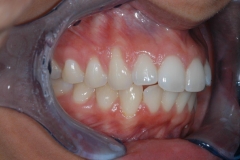

This young patient was self-conscious about the appearance of her short teeth and gummy smile. Through crown lengthening and tooth whitening procedures, we were able to create a beautiful, more mature smile.

Click on a thumbnail to view the before and after photos.